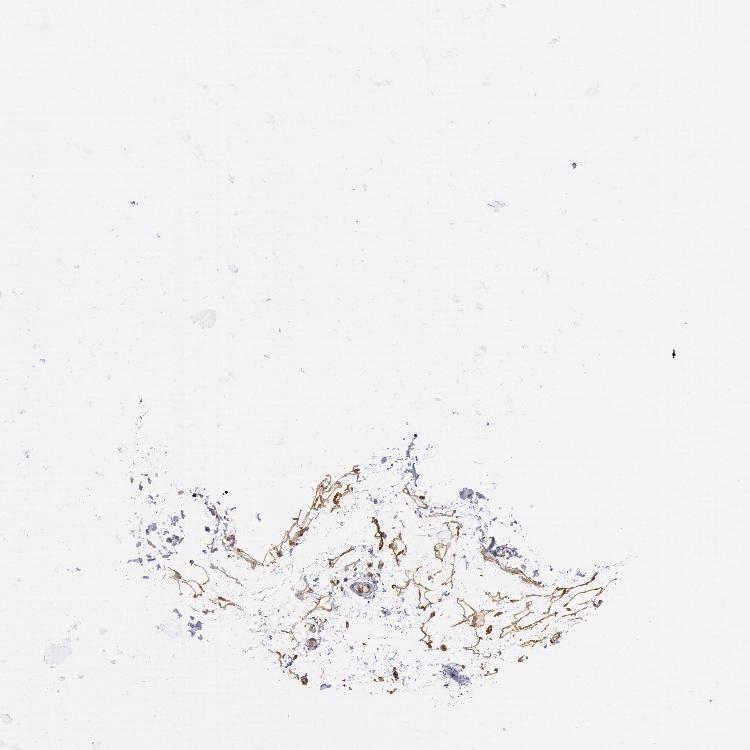

SOFT TISSUE 1 - Antibody stainingi

Antibody staining in the annotated cell types in the current human tissue is reported as not detected, low, medium, or high, based on conventional immunohistochemistry profiling in selected tissues. This score is based on the combination of the staining intensity and fraction of stained cells.

Each image is clickable and will lead to virtual microscopy that enables deeper exploration of all samples and also displays staining intensity scores, fraction scores and subcellular localization as well as patient and tissue information for each sample.

Antibody HPA001202

Fibroblasts Medium

SOFT TISSUE 2 - Antibody stainingi

Peripheral nerve Low